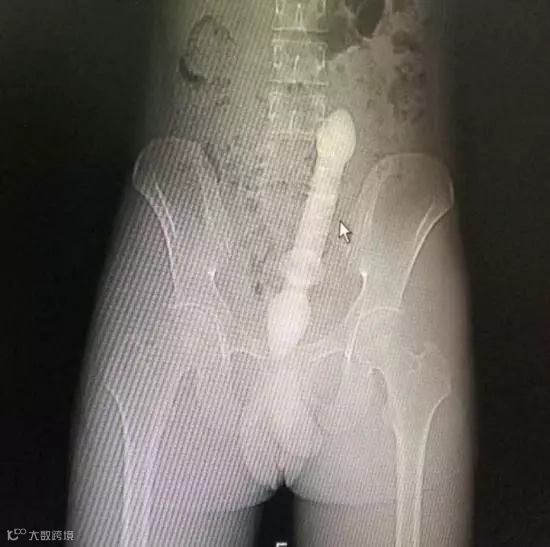

玻璃棒▽